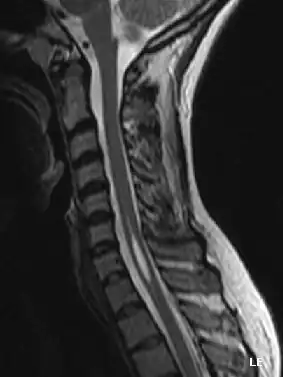

Syringomyelie is een zeldzame neurologische aandoening waarbij het ruggenmerg wordt aangetast, meestal vooral ter hoogte van de nekwervels, en het centrale kanaal in het ruggenmerg waardoor het wijder wordt.

De naam komt van het Grieks syrinx, een rieten buisje of fluitje en is gebaseerd op dit wijdere dan normaal kanaal dat bij pathologisch anatomisch onderzoek kan worden waargenomen. Tegenwoordig is de diagnose ook al bij levende patiënten te stellen door middel van MRI-onderzoek.